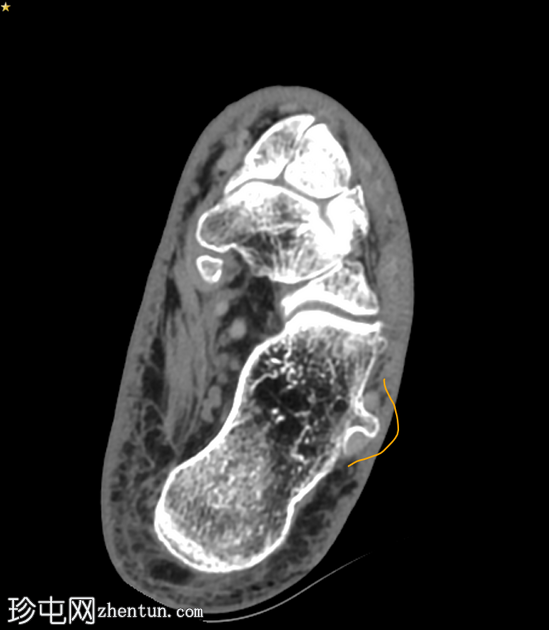

临床表现

跟骨外侧

疼痛

。

患者资料

年龄:65岁

性别:女

跟骨轴位CT

轴位

平扫

轴位骨窗